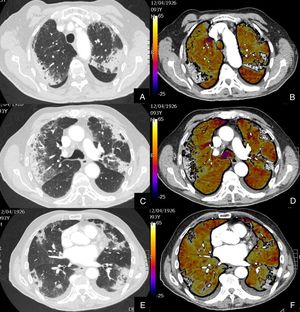

Paciente con COVID-19 con disnea, dolor torácico tipo pleurítico y elevación del D-dímero.

Imágenes axiales de una angiografía pulmonar con TC y mapa de yodo, con ventana de parénquima (A, C, E, G) desde lóbulos superiores hasta lóbulos inferiores y sus correspondientes imágenes del mapa de yodo (B, D, F, H).

Parénquima con extensa afectación en vidrio deslustrado y derrame pleural bilateral de pequeña cuantía. TEP unilateral en arteria lobar inferior derecha y segmentarias inferiores derechas (flechas). El mapa de yodo pone de manifiesto numerosas áreas de hipoperfusión (azules) parcheadas bilaterales (fundamentalmente en las zonas de pulmón afectado) por probable microtrombosis /alteraciones de la circulación en el lecho capilar.